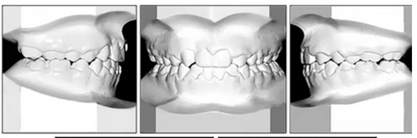

總體治療目標(biāo)已經(jīng)實(shí)現(xiàn)。病人的笑容和輪廓有所改善。咬合關(guān)系為I類磨牙關(guān)系,牙列整齊,牙尖交錯(cuò)關(guān)系良好。反合和中線偏移得以矯正,并實(shí)現(xiàn)了正常的覆蓋和覆合。上下牙弓的擁擠問題完全解決,并且完成后全景片顯示良好的牙根傾斜度。疊加顯示良好的縱向和垂直控制(ANB,3.5°; SN / GoMe,42.5°)和矯正上下頜前牙傾斜度(1 / SN,96°; IMPA,87°)(圖10 ; 表)。

在治療結(jié)束時(shí)沒有觀察到顳下頜關(guān)節(jié)紊亂的體征或癥狀,但發(fā)現(xiàn)了輕微的牙根吸收以及裂隙區(qū)域的骨頭輕度丟失。

治療持續(xù)3年,患者始終保持積極和合作??谇恍l(wèi)生很好。患者和她的父母都對(duì)結(jié)果感到滿意。經(jīng)過24個(gè)月的保持后,咬合保持得很好(圖11 ; 圖12)。在上牙弓中,應(yīng)用固定舌側(cè)保持器以防止任何復(fù)發(fā)傾向。在下牙弓中,治療后拔除第三磨牙。